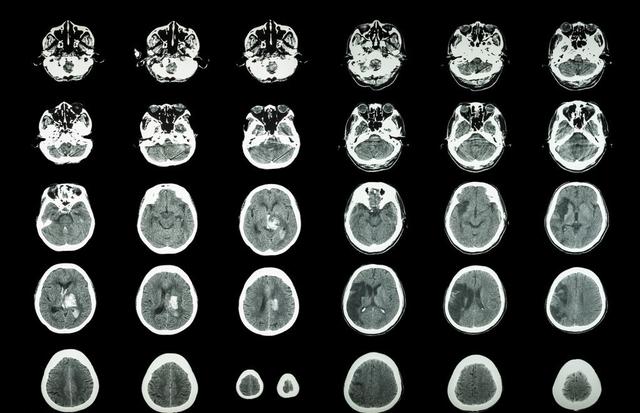

所说的脑中风,又称为脑卒中,其中20%为出血性脑卒中(脑出血),80%为缺血性脑卒中(脑梗塞)。两者都会造成大脑神经细胞的死亡,所表现出来的临床症状很相似,只有进行CT或是核磁检查才能正确辨别,从而采取正确的治疗手段。